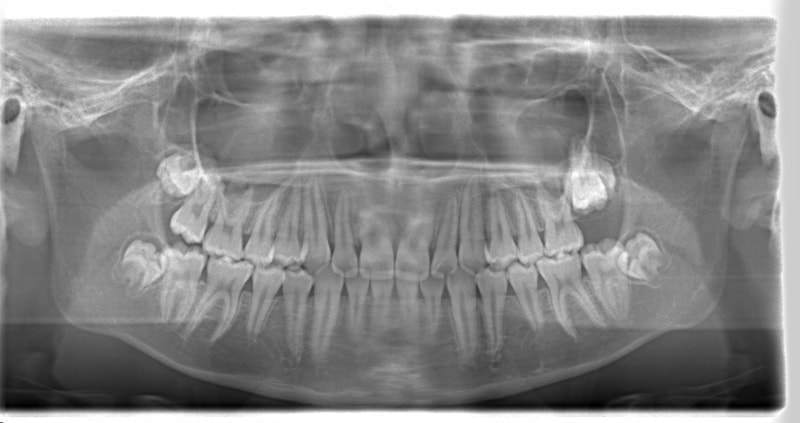

小児期ケース:反対咬合+上顎両側3番埋伏歯

(受け口+3番目の永久歯が左右両方とも埋まってしまい、はえてこない)

治療法:上顎急速拡大装置+クリアスナップ+フェイスマスク+上顎3番は開窓牽引CT写真にて位置確認

治療前

FX(フェイシャルアキシス)は85度なので東洋人の平均値に近く、下顎が前方に過剰成長するリスクは強くはありません。

しかしやはり上顎は劣成長で、下顎が優位な状態ではあります。

上下顎のギャップはありますが、顔面自体の幅径は良好な値を示していますので、スペース不足は拡大することによって解決できポテンシャルはあると考えられます。

左右の非対称もさほど強くありません。

骨年齢は実年齢よりも低めなので、今後下顎の旺盛な成長が見込まれます。

検査時のレントゲン分析では、上下顎の関係は、上顎の劣成長があり下顎前突傾向という値がでておりましたが、前歯ジャンプ後はフェイスマスクの効果もあり、上下顎の関係は正常化しています。

上顎が若干優位になっていますので、今後の下顎の成長のための貯金になっているくらいです。